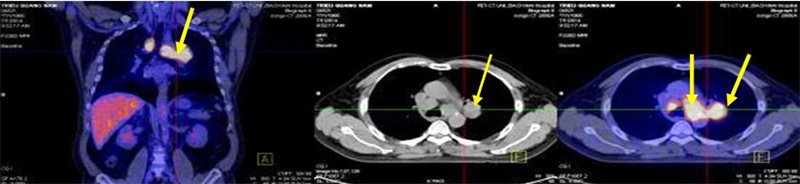

Bệnh nhân:chụp PET/CT lần 2 đánh giá sau 6 chu kỳ hóa chất (có đối chiếu với lần chụp trước khi điều trị).

Sau điều trị: hết u và hạch di căn

Sau điều trị: không thấy nốt mờ và hạch di căn trung thất

Trước và sau điều trị hóa chất 6 chu kỳ

Như vậy, bệnh nhân đã đáp ứng tốt sau điều trị với các triệu chứng lâm sàng và cận lâm sàng cải thiện rõ rệt.